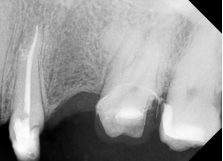

2. Glide path mecanizado con progresión controlada usando la lima 016 (R-Shaper)

Posteriormente, se procedió a la creación de un glide path reproducible mediante la lima 016 del sistema R-Shaper.

Esta lima demostró un comportamiento clínico favorable durante esta fase, permitiendo una progresión controlada incluso en el conducto vestibular con doble curvatura en bayoneta.

Las limas de níquel-titanio con tratamientos térmicos, como las del R-Shaper, exhiben mayor flexibilidad y resistencia a la fatiga cíclica en conductos curvos, lo que es coherente con la evidencia científica actual.

Este glide path mecanizado no solo facilita la negociación apical, sino que también previene complicaciones como la fractura instrumental, asegurando una transición suave hacia la conformación principal.